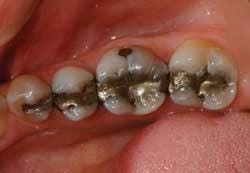

The time to begin the process of going metal-free has come upon the dental profession. The patients are asking to have their old restorations replaced with something more esthetic and biocompatible (Figures 1 and 2).

As esthetic concerns continue to dominate the patient’s willingness to accept dental treatment, choosing the proper and desired shade is of ultimate importance. No patient really cares whether his or her amalgam filling matches their metal crown, but porcelain restorations are expected to match. If the patient has opted to whiten his or her teeth, this is obviously done prior to restorative treatment.